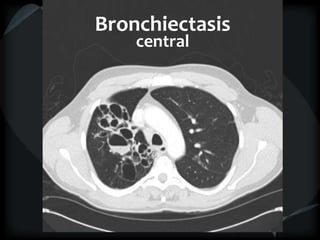

Bronchiectasis

Vessel at wall of cyst – signet ring

Cyst stacked in tubular orientation

Cyst stacked in branching pattern

Dilated, irregular, thickened airways

Mucus-filled airways

Diameter of peripheral airway to accompanying

artery = >1

● HGG ● CD

● ABPA ● tracheobronchomegaly

● CF ● α-1 antitrypsin deficiency

● DPB

central